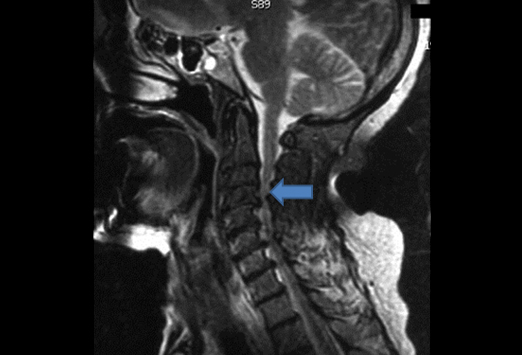

Es la compresión de la médula espinal en la zona del cuello, la palabra compresión quiere decir presión sobre la médula espinal.

La Mielopatía Cervical Espondilótica puede afectar adultos y mujeres mayores 50 y 55 años.